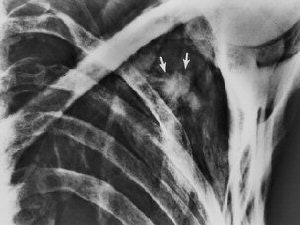

![]() |

| Irregular opacity (arrows) in the left shoulder retrospectively detected on a conventional frontal radiograph of the chest (obtained on September 26, 1991) has the general configuration of an arrowhead. Also in retrospect, the arrowhead is visible on the radiograph obtained on May 25, 1993 (top). Fig. 8, 21, Murphy WA, zur Nedden D, Gostner P, et al. "The Iceman: Discovery and Imaging," Radiology 2003; 226:614-629. |